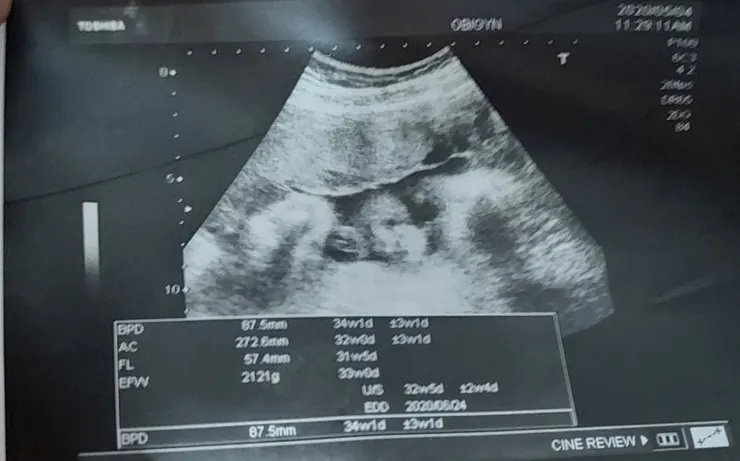

2020.5.04(一)AM9:30 (34w1d--2121G)

2020.5.04(一)PM13:00(34w1d--2121G)

接下來要兩週報到一次,今天30週來妊娠糖尿檢查,還有產檢,小孩已經2100,天啊要如何胖媽媽不要胖小孩啊,而且醫生說寶寶的頭大三週,是不是沒多久就可以生了,我看已經八公分了,這樣生的出來嗎?但是醫生卻沒有叫我少吃,還是他覺得反正生不出來就是剖腹,好煩喔,寶寶可以不要一直變大嗎?天主幫忙一下啦,自己覺得臉看起來很可愛,哈哈,大家有看到臉嗎?